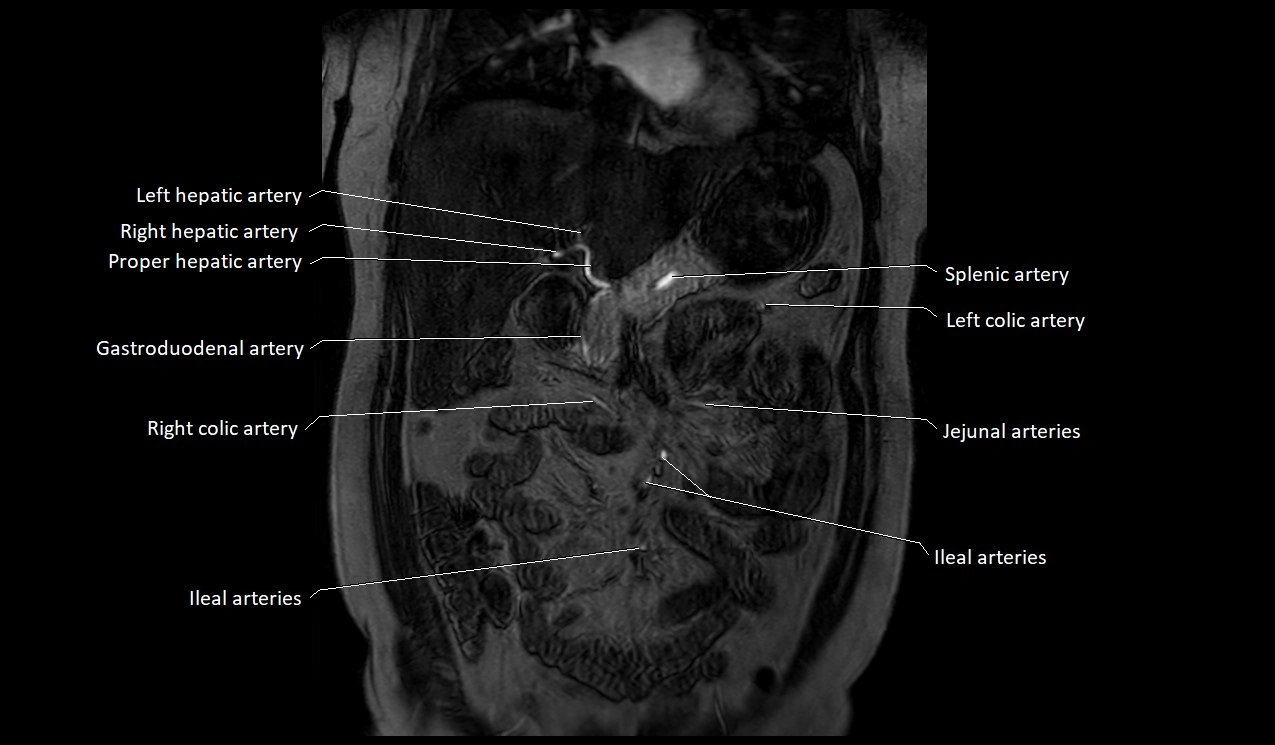

MRI Appearance

T1-weighted images:

Artery appears as a small linear hypointense flow void coursing over the superior pubic ramus

Seen within bright perivascular fat of pelvis

MRA Pelvis with Gadolinium:

Clearly delineates the origin, course, and anastomoses of the accessory obturator artery

Identifies connection with inferior epigastric artery, external iliac artery, or obturator artery

Excellent for detecting vascular variants prior to surgery

Useful in mapping pelvic vasculature in trauma, tumor embolization, or preoperative planning